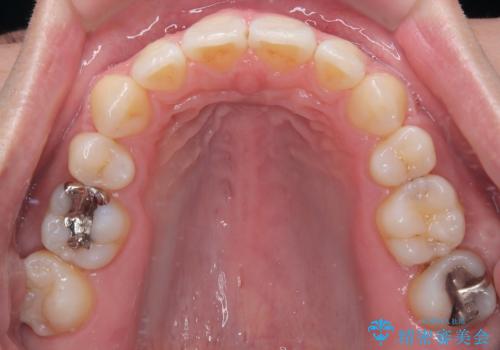

左上はアンカースクリューを併用することでスムーズに抜歯スペースを閉じることができました。

口元の突出感もなくなり満足されました。